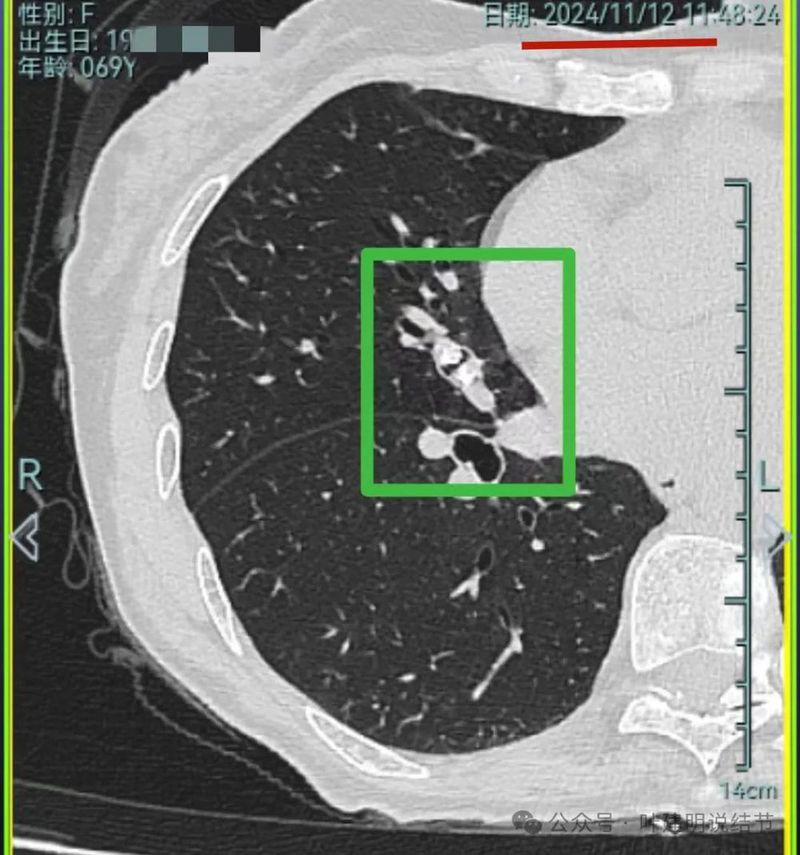

再看2024年11月复查的情况:

病灶1仍磨玻璃稍高密度,有血管进入,大小无显著进展,但密度从开始到现在是有所进展的。

病灶2与5年前比也说不上明显进展。

病灶3仍是混合密度,伴有收缩力,但实性部分并无聚拢性,也不是密度很高的样子。

病灶4仍钙化且无明显进展。

病灶5实性成分明显较前增多明显,总体上有进展,但这个病灶主要周围比较散,显得有些模糊。

原病灶6左上这处消融后瘢痕形成。

我想我们这样也来考虑问题:1、左侧已经手术的确诊是肿瘤性质,左上已经消融的也是随访持续存在的磨玻璃密度结节,虽然没有病理依据,仍然要考虑广义上来讲的肿瘤范畴,看了以前的片子,从2019年到2023年并没有显著的进展,大概是肺泡上皮不典型增生可能性大。右侧的也有磨玻璃结节与混合磨玻璃结节考虑是肿瘤范畴的。所以总体上两肺多原发早期以磨玻璃为表现的肺癌,整体风险都不大。2019年切除的左肺下叶病灶也是纯磨玻璃密度,其实如果继续随访或者只做楔形切除也并没有什么关系。这说明体质本身或者致病的因素,就是容易长磨玻璃肺癌的,即便把目前发现的都解决,后续仍可能再有新的。原因不明,致病因素仍在。2、右肺上叶红色之处从2019年开始,是逐渐进展的,当然即便是现在,也不是说危险就已经很大,考虑仍然是原位癌或者微浸润性腺癌可能性大;中叶蓝色这处乍一看像至少是微浸润,但前后对比以后发现从2019年到现在,几乎没有显著进展,这样的话慢性炎伴肺泡上皮增生或者伴纤维增生也是有可能的,至少风险并不能认为大;右肺下叶黄色这一处,使纯磨玻璃密度,整体轮廓与边界清楚,考虑是肿瘤范畴的,不典型增生可能性较大,也有可能原位癌,随访稍有进展,风险仍然不大;中叶绿色这处是慢性炎伴钙化的,靠近叶裂的地方也像慢性炎,但此处随访有所进展。不过因为有卫星灶,整体显得比较散,所以虽然恶性可能性较大,但也不能完全除外炎性的可能性。当然如果此灶确实恶性,那风险则相对较其他进展缓慢的要高一些。从目前右侧所在的这些病灶来讲,真正有一定的风险而且最为确切的是红色这处,而且应该也没有到浸润性腺癌或者说不处理会要转移很危险这种程度。3、明确了多原发早期肺癌没有办法预防与控制,也明白了目前已经存在的较明显的这些病灶总体风险的高低。我们再来考虑需不需要近期干预处理。左侧既手术过又消融过,右侧的多发病灶目前又还没有到危险很高的程度,又没有办法预防后续再有新的病灶。我个人偏保守,我觉得仍然可以半年复查随访,如果最具风险的病灶有进展并且不处理可能导致不良后果,到这样的程度再来考虑综合如何处理干预便可。4、假如右侧我们予以处理,上叶红色的以及中叶蓝色的都可以楔切,但绿色考虑良性的再进展或以后像恶性时怎么办?而若中叶切除加上叶楔切,在左侧已经手术过的情况下肺功能影响相对也不小,何况右下比较中间的位置还有桔色这处呢。当然右下这处得考虑消融。所以,我的想法还是能熬再熬下,待其他监测有变化再通盘考虑。意见供参考!